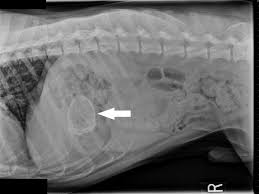

Ce fac stăpânii când nu au jucării sau bețe la îndemână? Le aruncă pietre pentru aport. Adesea, fapt observat și de stăpâni, câinele înghite piatra.